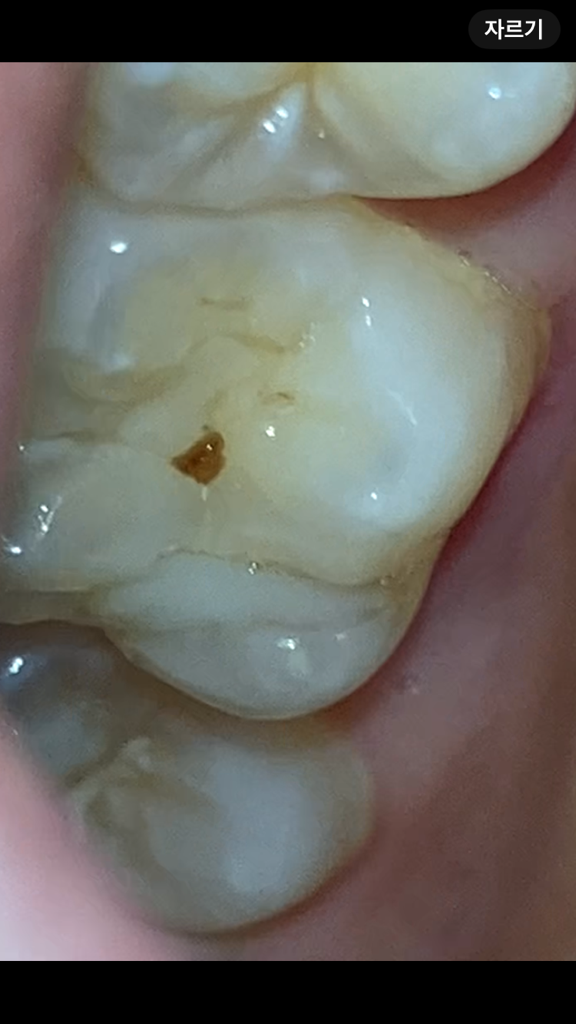

이거 혹시 치료해야 하는 충치인가요

블루베리를 간식으로 먹고, 양치를 한 후에 입을 다무는데 오른쪽 어금니쪽이 왼쪽보다 뭐랄까 서로 딱 맞물려서 닫히지 않고 잘 안닫히는듯한?뭔가 사이에 무언가가사아알짝 껴있는듯한?그런 매우매우 미세한 이물감이 있어서 확인했더니 얘가 있네요

블루베리 씨겠거니 껍질이겠거니 하고 이쑤시개로 벅벅 긁었는데도 안닦이고..딱 중심부같은 곳을 눌렀는데 뭔가 그 어금니 안에 지잉 하는 그런뭐랄까 절대 아프진 않은데 뭔가 느껴지는 그런게 있었어요

예전에 치료를 한곳이 깨지면서 안쪽으로 2차 충치가 생긴거 같습니다. 치과에 가셔서 다시 치료를 받으시는게 좋을것같습니다 .

현재 블루베리의 잔여물이 치아의 주름에 낀것으로 보입니다. 억지로 빼내는 경우 치아에 손상이 가기에 치과에 방문하여 제거를 권하며, 치아주름을 메꾸는 치료를 받는 것이 충치 예방에 도움이 됩니다.

사진으로 봤을 경우에는 이물질이 치아 사이에 껴 있는 것으로 보입니다. 시간이 지나면서 껴있는 음식은 자연적으로 빠지게 되는데 시간이 지나도 빠지지 않거나 이물감이 계속해서 진다면 치과에서 진료를 받아보는 것이 좋습니다.

현재로선 음식물의 가능성이 아주 높습니다. 확인차 계속 씹게되면 치아 고랑으로 더 깊게 음식물 찌꺼기가 박히게 됩니다. 식편압입으로 인해 이상한 느낌이 유발될 수 있습니다. 양치질로 제거가 안된다면 치과를 내원해서 스케일링을 받아보시기 바랍니다.